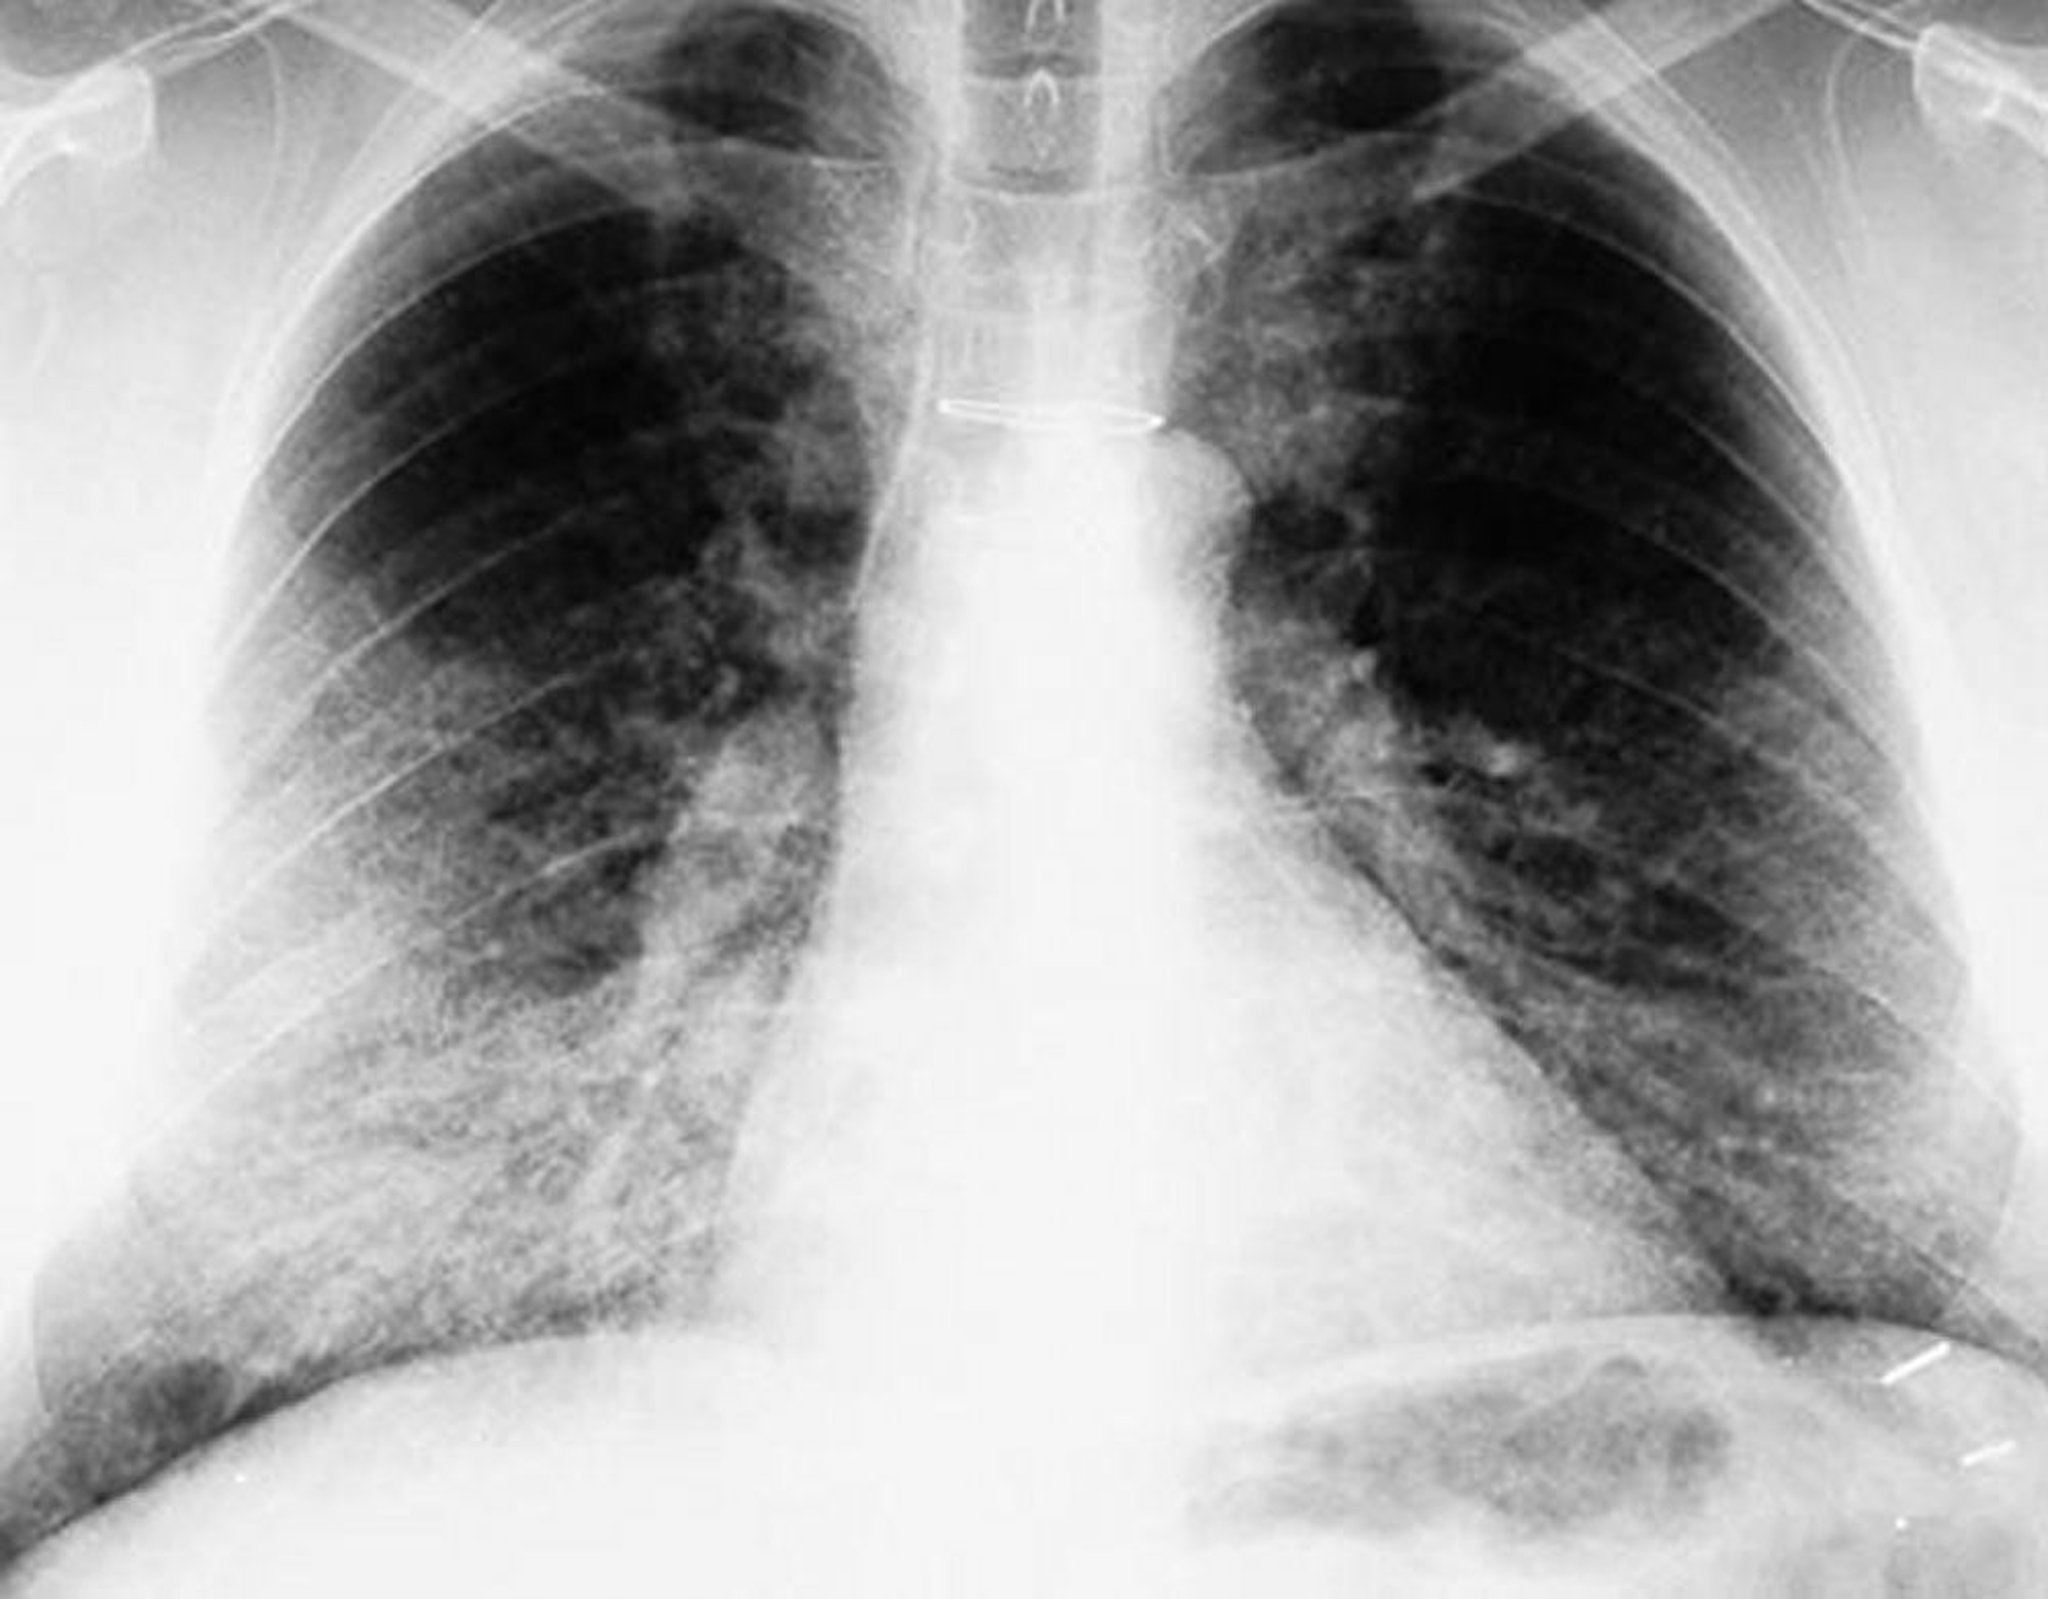

Protéinose alvéolaire pulmonaire (radiographie de thorax)

La radiographie de thorax montre des opacités bilatérales, principalement basales.